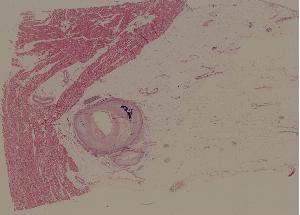

9. Healing of skin by first intention